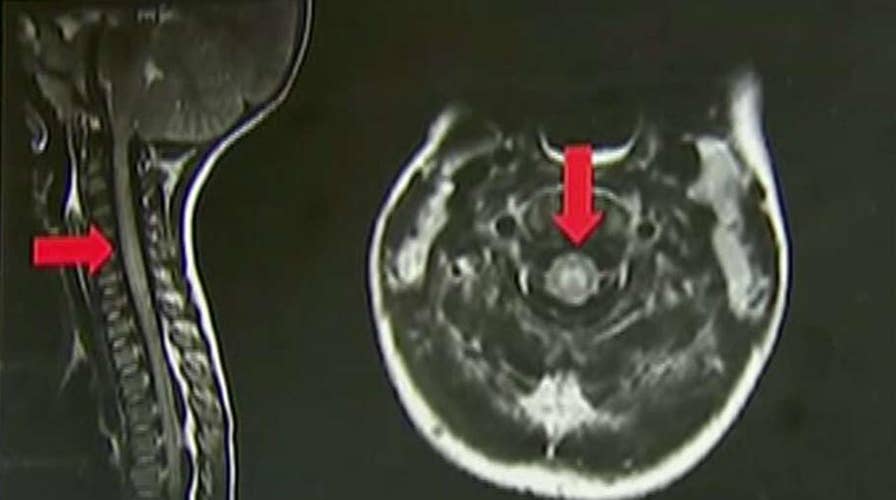

Health officials says the paralyzing illness acute flaccid myelitis has been reported in 22 states; Laura Ingle reports.